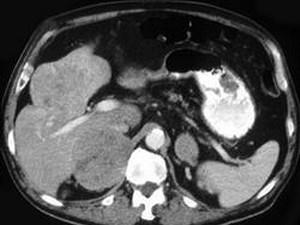

问题 男性,60岁,曾患乙肝,肝硬化多年,右上腹胀痛1月余,AFP为80.8μg/L,CT检查如图所示,最佳的诊断是 ( )

选项 A.肝结节性增生、右肾上腺瘤 B.肝、右肾上腺均为转移瘤 C.肝癌右肾上腺转移 D.肝腺瘤、右肾上腺腺瘤 E.肾上腺癌肝转移

答案 C